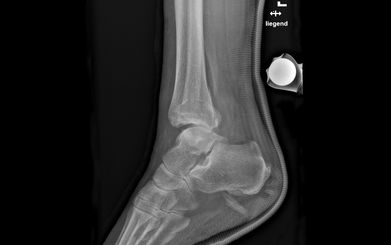

Das obere Sprunggelenk (OSG) besteht aus drei aneinander angrenzenden Knochen, dem Schienbein (Tibia), dem Wadenbein (Fibula) und dem Sprungbein (Talus). Funktionell ähnelt es einem formstarken Scharniergelenk, das eine Beugung (Flexion) von ca. 40° und eine Streckung (Extension) von ca. 20° zulässt. Die beiden Knöchel – im Fachjargon Malleolen genannt – bilden je einen Zinken der sogenannten Malleolengabel, die das Sprungbein stabilisierend umschliesst. Die Malleolengabel wiederum wird durch ein starkes Band (Syndesmose) zusammengehalten. Für die seitliche Stabilität des OSG sorgen die an den beiden Malleolen entspringenden Seitenbänder.

Unter einem Knöchelbruch – auch Sprunggelenkfraktur oder Malleolarfraktur – wird ein Bruch (Fraktur) des inneren und/oder äusseren Knöchels verstanden. Oft treten dabei auch Begleitschäden an Bändern, Knorpeln oder Sehnen auf.

Die Schmerzen und die Schwellung über dem Aussen- und/oder Innenknöchel lassen bei der Untersuchung häufig auf eine Bandverletzung oder einen Bruch schliessen. Die definitive Diagnose wird jedoch erst anhand eines Röntgenbilds gestellt. Eine weiterführende Diagnostik mittels Magnetresonanztomographie (MRT bzw. engl. MRI für magnetic resonance imaging) bleibt unklaren Fällen mit hohem Verdacht auf zusätzliche Syndesmosenverletzung vorbehalten. Bei komplizierten Brüchen dient eine Computertomographie (CT) der besseren Erkennung oder dazu, knöcherne Zusatzverletzungen auszuschliessen.